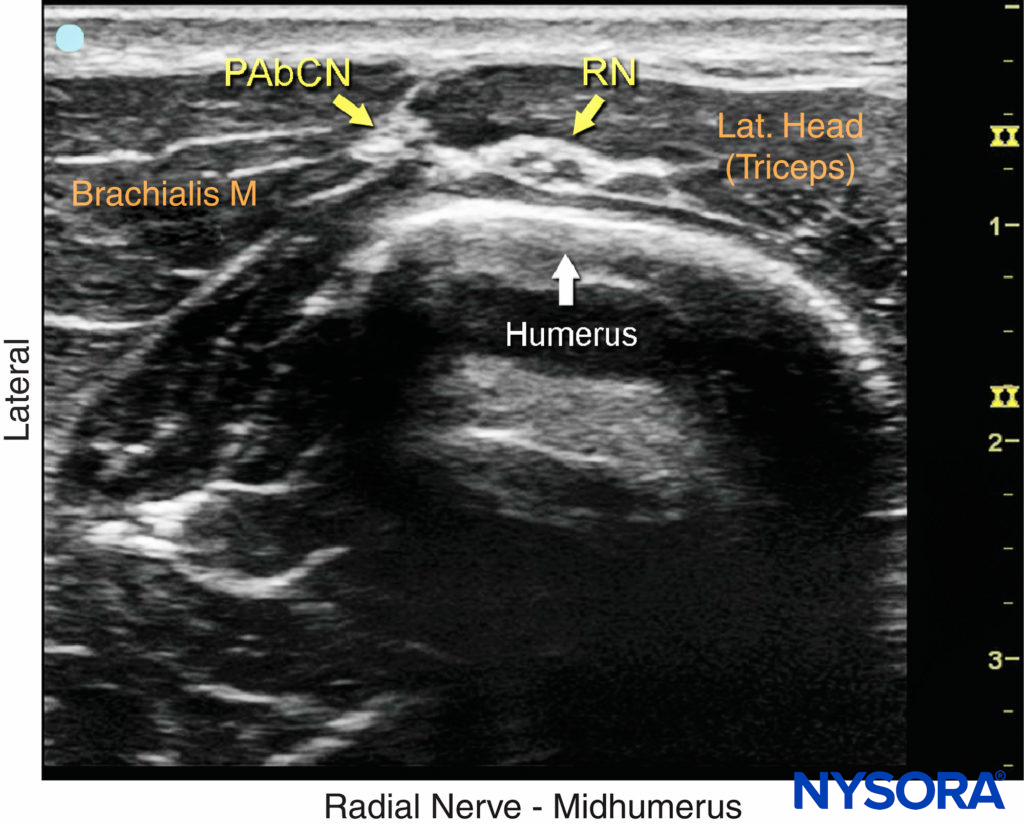

FIGURE 3. Sonoanatomy of the radial nerve (RN) in the spiral groove of the humerus. PAbCN, posterior antebrachial cutaneous nerve.